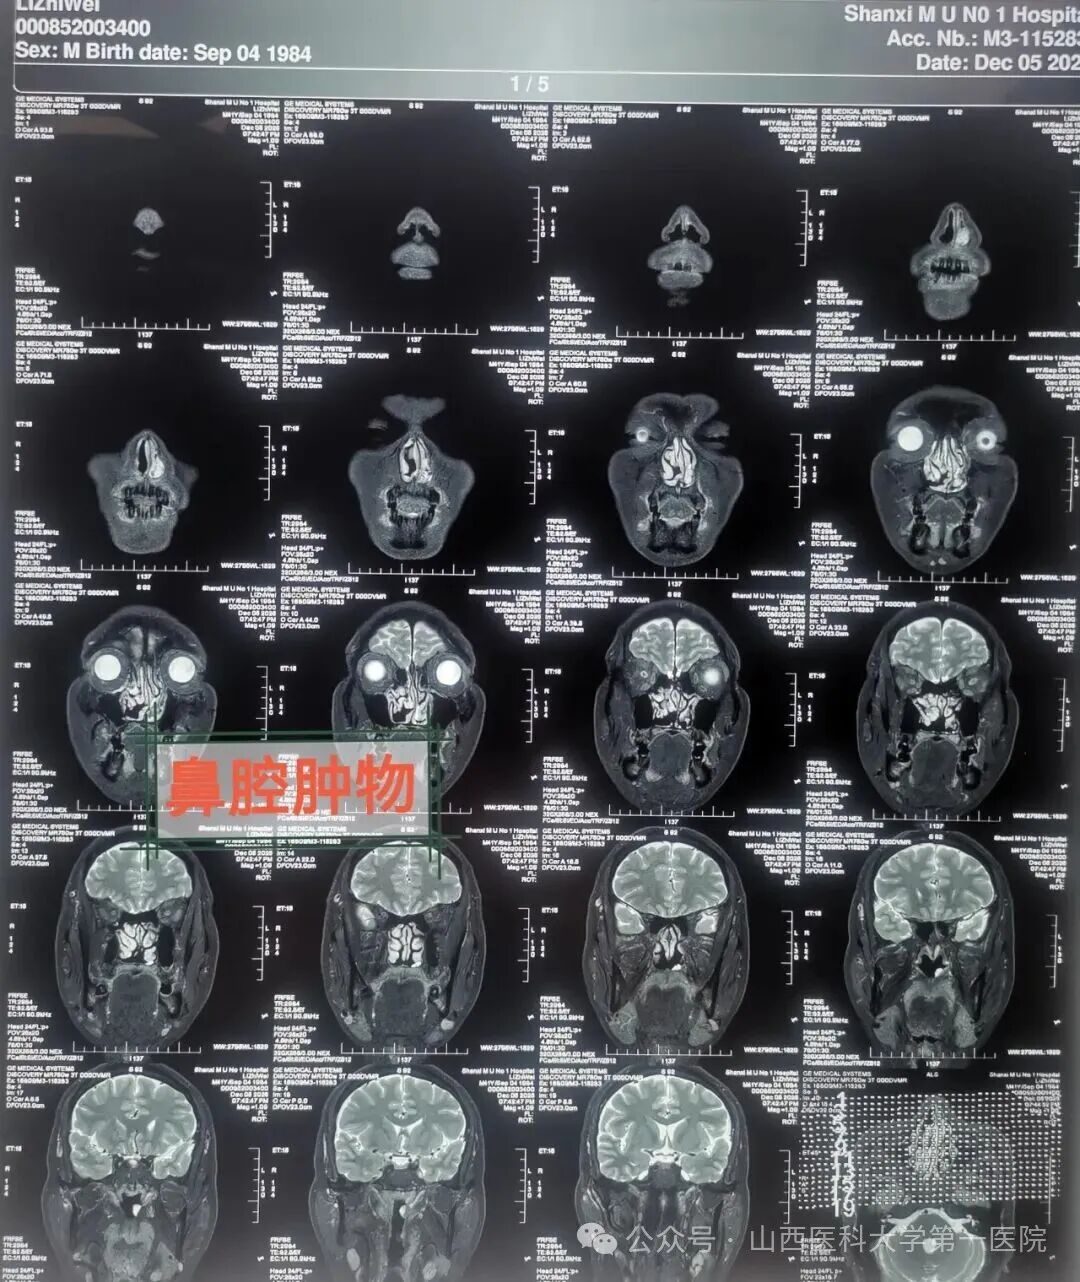

41岁的赵先生患过敏性鼻炎多年,有时还会鼻出血,症状重时需要药物治疗,基本可控制缓解鼻部常见症状。最近3月以来,鼻部症状渐加重,药物治疗效果差,莫名奇妙有特殊嗅味,出现鼻涕中带血丝,嗅觉明显减退,有时还会出现鼻出血,当地医院影像学检查鼻窦CT检查报告为:鼻腔鼻窦病变,随后就诊于山西医科大学第一医院耳鼻咽喉-头颈外科,通过鼻内镜检查及医学影像学检查,初步考虑为鼻腔恶性肿瘤。办理住院手续后完善各项检查后,安排手术治疗,全科病例讨论后确定外科手术治疗方案,由柴向斌教授主刀、王洋术中配合,鼻腔肿瘤已侵犯鼻腔黏膜与鼻中隔黏膜,采用鼻内镜鼻腔进路手术,暴露术野,明确肿瘤界限,完整切除肿瘤。

柴向斌强调,患者出现渐进性鼻塞、鼻出血等症状时,要及时就诊,尽量避免漏诊与误诊。医生会对患者进行全面体格检查,然后可能建议患者做CT、MRI、病理检查等,以明确诊断,为后续制定科学、个性化的治疗方案奠定基础。